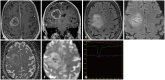

The imaging and clinical management of patients with brain tumor continue to evolve over time and now heavily rely on physiologic imaging in addition to high-resolution structural imaging. Imaging remains a powerful noninvasive tool to positively impact the management of patients with brain tumor. This article provides an overview of the current state-of-the art clinical brain tumor imaging. In this review, we discuss general magnetic resonance (MR) imaging methods and their application to the diagnosis of, treatment planning and navigation, and disease monitoring in patients with brain tumor. We review the strengths, limitations, and pitfalls of structural imaging, diffusion-weighted imaging techniques, MR spectroscopy, perfusion imaging, positron emission tomography/MR, and functional imaging. Overall this review provides a basis for understudying the role of modern imaging in the care of brain tumor patients.